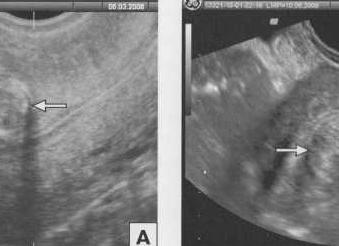

Какое-то образование в организме может показывать сниженную акустическую плотность, выглядеть на экране темнее соседних тканей. Этот феномен и называется гипоэхогенностью, то есть уменьшенной плотностью. В этом участке продвижение ультразвука происходит медленнее. Чаще всего такое явление имеет жидкую структуру: это может быть, к примеру, киста. Врач не сможет сразу сказать точный диагноз.

Очень важными факторам являются форма и размеры узла. В случае если гипоэхогенный участок имеет округлые контуры, значит, в исследованном органе могут присутствовать некоторые виды опухолей. Затемненные зоны, выявляемые в ходе исследования, иногда являются нормой и свидетельствуют о доброкачественном образовании, например, в груди во время лактации. Гипоэхогенное образование может находиться в различных органах: поджелудочной железе, печени, почках, матке, яичниках, молочной железе и др.

Если же гипоэхогенная зона имеет нечеткую форму, то это может свидетельствовать о карциноме. Во время этого можно наблюдать расширенную полость матки и присутствие боковой тени. Если образования были выявлены рядом с плодным яйцом и имеют низкую плотность, то это является предвестником начавшегося выкидыша.

Это свидетельствует о том, что под плодом происходит скопление крови, и в этом случае необходимо немедленное вмешательство врачей.